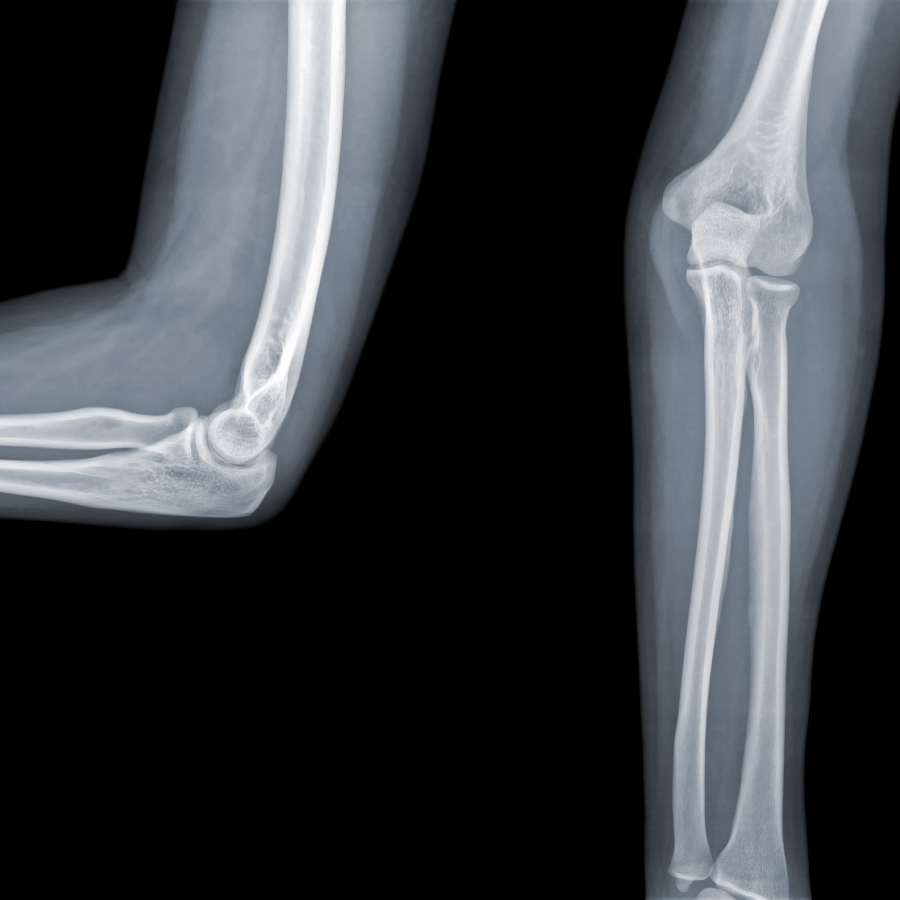

Codo